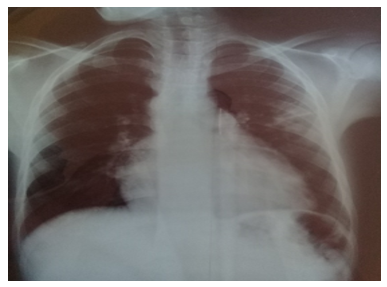

El paciente recibió antibioticoterapia mediante ceftriaxona 1 gramo y claritromicina 500 mg por vía intravenosa cada 12 horas por 10 días; además, se le administró hierro parenteral 100 mg tres veces por semana, evolucionando de forma satisfactoria desde el punto de vista clínico, humoral e imagenológico (figura 4).

Figura 4.Radiografía de tórax vista postero anterior de evolución del paciente

Fuente: historia clínica del paciente.